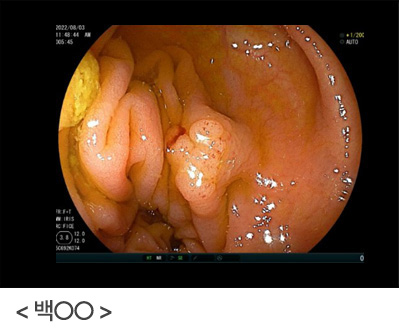

정기적인 위내시경을 받으셨더라면 조기에 발견했을 텐데, 안타까운 경우입니다. 식도암은 음주와 흡연이 가장 중요한 위험인자이며, 특히 흡연량이 많아질수록 위험도도 높아지는 것으로 알려져 있습니다. 음식물 섭취 시 걸린 느낌, 소화장애가 지속된다면 반드시 위내시경 검사를 통해 이상 여부를 확인해 보시기 바랍니다.